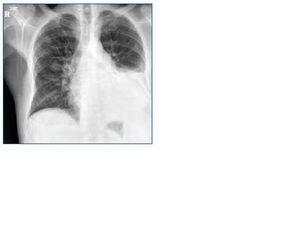

En febrero 1995 presentó brote vasculítico que cursó con úlcera necrotizante en maleolo interno de pie derecho y lesiones purpúricas. Faringitis y hemorragia intralveolar difusa, con patrón radiológico de ocupación alveolar bilateral.

A nivel pulmonar puede haber nódulos, atelectasias, derrame pleural e infiltrados. Es frecuente la cavitación5.

En septiembre de 2007, 23 años después del diagnóstico de Enfermedad de Wegener y coincidiendo con cuadro catarral, se realiza una radiografía de tórax de control objetivándose derrame pleural izdo que no se había evidenciado en TAC de control de enero (fig. 1). Los estudios inmunológicos fueron negativos. Se solicitó nuevo TAC que confirmó la presencia de derrame pleural izdo. y múltiples nódulos pulmonares. Se decidió realizar toracocentesis diagnóstica y evacuadora. El resultado anatomopatológico del líquido pleural que bioquímicamente mostraba características de exudado de aspecto hemático fue de Adenocarcinoma de pulmón. Iniciándose tratamiento paliativo.

Figura 1.